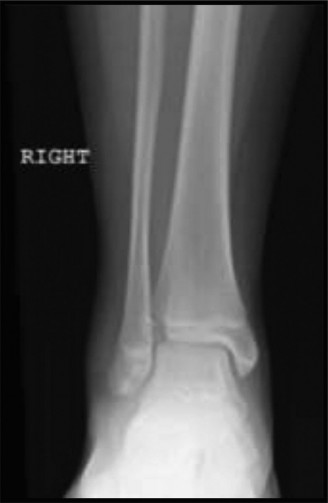

CASE 13 A 56-year-old homemaker fell down the steps of her basement injuring he…